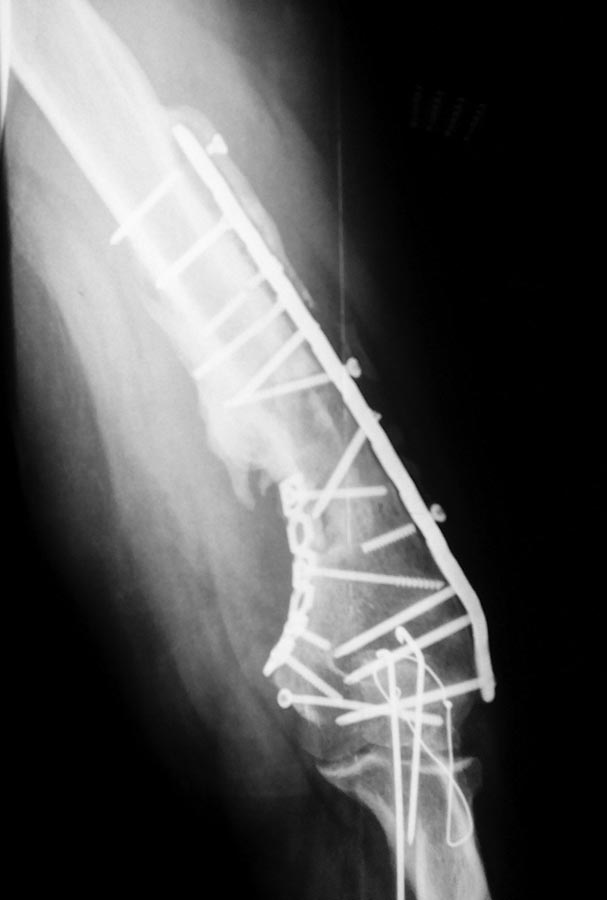

Уважаемые коллеги, хотелось бы услышать вашего мнения по поводу непростого случая несросшегося перелома плечевой кости. Пациент 44года в 2013г закрытый многооскольчатый перелом дистального отдела правой плечевой кости. Остеосинтез пластинами в одной из столичных клиник. В п/о периоде нейропатия лучевого и локтевого нервов, за 10 месяцев лучевой полностью восстановился, локтевой почти - небольшие парастезии в мизинце остались. Обратился ко мне летом 2015г (по совету общего знакомого), до этого обращался в учереждение где был выполнен остеосинтез, но в силу ряда причин не пожелал там оперироваться (кстати предлагалось только удаление металлофиксаторов). Пациент без вредных привычек (разве что переедание), из сопутствующей патологии ожирение (вес 160 кг рост 190см), сахарный диабет (невысокие цифры).В августе 2015г удаление металлофиксаторов, невролиз лучевого нерва, реостеосинтез (той же) пластиной, но в положеном задне-латеральном положении. При операции удалено около 50 куб. металлоза, при ревизии в месте несращения были подозрительные творожистые включения, но кость выглядела здоровой,все многократно промывал антисептиками, иссечены рубцы, края отломков адаптированы друг к другу по типу замка - зона контакта большая, суммарно кость укорочена около 1,5 см. Перед операцией планировал ставить 2 пластину медиально, но до операции консультировался с более опытными коллегами и ставить вторую пластину не рекомендовали, все же заказал, но не поставил... операция заняла в целом 7,5 часов то ли устал, то ли действительно фиксация показалась достаточной учитывая характер сопоставления отломков (ну не суть важно что сделано то сделано). Был установлен дренаж, но наследующий день он забился - удалил, опасаясь инфицирования довольно агрессивно промывал хлоргексидином, на 5 сутки на коже нижней трети плеча по наружной поверхности появился пузырь 10 на 10 см, промывать перестал. Рана зажила первичным натяжением. Дефект кожи после фликтены постепенно заживает (от пересадки кожи пациент отказался). После операции нейропатия лучевого нерва (целостность сомнению не подвергается был выделен весь) за 2 месяца значительная положительная динамика. Иммобилизирован на косынке. В сентябре ниже локтевого отростка появилась небольная безболезненная припухлость по ходу рубца, была вскрыта и получен гной (со слов коллеги я был в отпуске), через 4 дня я видел рану гноя не было отделяемое серозное больше похоже на синовиальную жидкость (предполагаю что идет от локтевого отростка к которому было пришито сухожилие трицепса тисорбом они часто текут по личныим наблюдениям, но не факт...), неоднократно посев роста нет, кровь спокойная, температуре нет соответственно. 2 месяца после операции (22.09.15г) КТ контроль - все стабильно. Две недели назад разрешил иногда снимать косынку но рукой не пользоваться. Неделю назад пациент стал говорить что появился хрукт. Рентген контроль - перелом 2х винтов нестабильность вторичное смещение. Предварительно планирую брать на ревизию удалить винты с проксимального отдела, репозиция остеосинтез и дополнительно медиальная реконструктивная? пластина.

1. По представленной информации не совсем понятен смысл выполненной вами в августе операции. На передне-задней рентгенограмме убедительных признаков несращения нет. Было бы неплохо выложить вторую проекцию - возможно она действительно продемонстрирует несращение. Прикрепленная КТ не читаема (и наверное это КТ за сентябрь). (Кстати желательно уменьшить размер файлов согласно инструкции на сайте - очень долго грузятся).

Пока же кроме варусной деформации, нескольких сломанных винтов и костных наростов (которые можно трактовать как признаки инфекции) на прямом снимке ничего страшного не видно. Такая деформации клинически вряд ли будет играть роль у пациента весом 160 кг.

Может не так хорошо видно, но ВСЕ винты были сломаны и из 7,5 часов 5 ушло на удаление и невролиз, может не так хорошо видно но ВСЕ винты были сломаны, все было в грубом рубцовом конгломерате и металлозе, промывал хлоргекс и бетадином, фликтеной назвал условно потому как предполагаю что из-за выраженного отека и плюс дополнительно накачивал промывая остро появился пузырь отслоивший кожу (как его по другому назвать не знаю), насчет зачем полез, да почему то многие считают что пациенту нужно было ждать пока не сломается пластина, компрессию дал, между фрагментами винт поставил на снимке видно(хотя думаю не стоило он и сломался). И снимок за 6 месяцев до последнего где было только 2 винта сломано выкладываю.

Повторно планирую ставить эту же пластину как минимум из тех соображений что бы не удалять винты из дистального отломка и максимально сократить время операции, к тому же пластина хороша, кто не заметил это заднелатеральная синтезовская пластина, которая на мой взгляд оптимальна здесь поэтому и не стал другие ставить.

Насчет второй медиальной пластины. Нет в ней смысла кроме потенциального вреда: и мягкие ткани дополнительно мобилизовывать надо, и время операции увеличится. На сей момент несращение в нижней трети плеча, а не в метафизарной или суставной зоне.